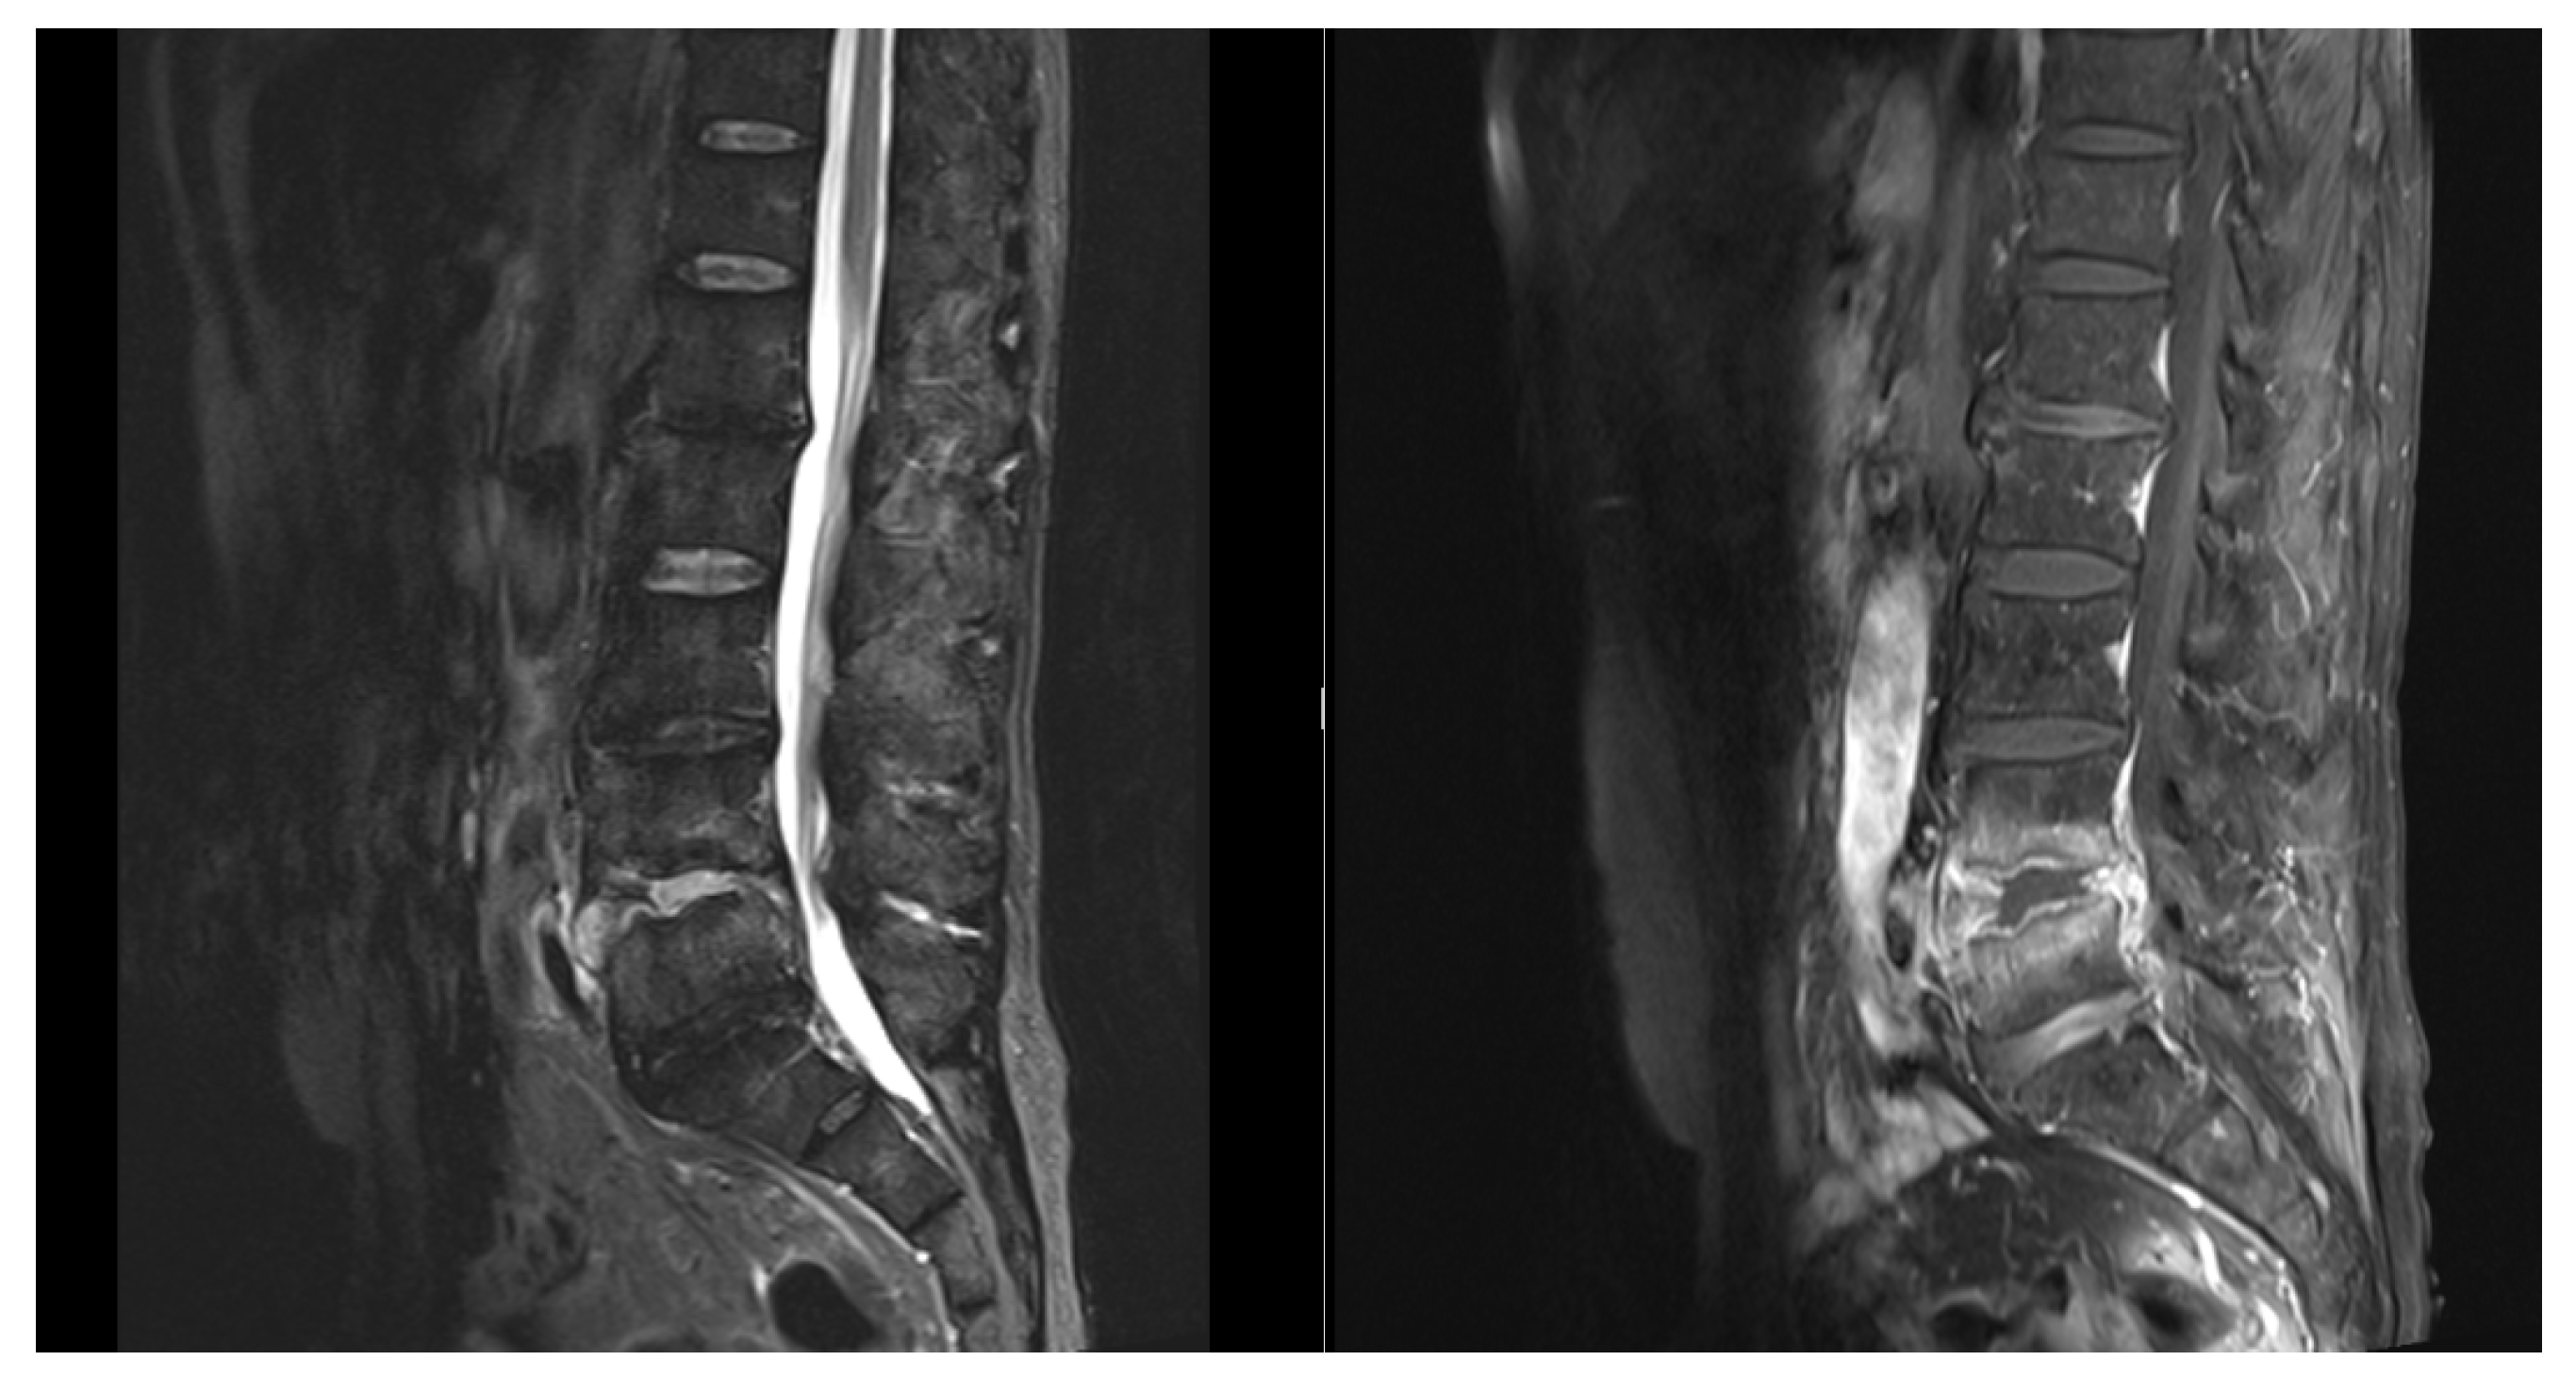

Figure 4. T1+C, T2 MRI showed fluid signal in L4-5 disc space with adjacent heterogeneous enhancement including margin of disc, epidural space, and adjacent endplates. Right paraspinal extension of the fluid and bilateral paraspinal infiltration was noted. Thecal sac is compressed, especially right part.

Figure 5. After minimally invasive transforaminal lumbar interbody fusion with TM cage and autologous & artificial bone grafts (L4/L5, via right side) and percutaneous posterior fixation with pedicle screws (L4 and L5, bilateral).